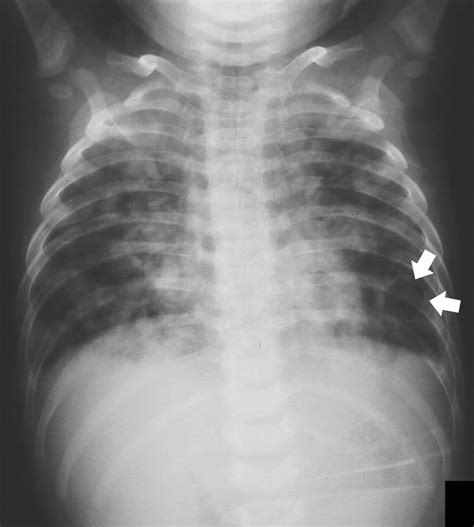

Tuberculosis is a bacterial infection caused by Mycobacterium tuberculosis, primarily affecting the lungs but also capable of spreading to other parts of the body. Symptoms can include persistent cough, chest pain, and weight loss. Early detection is key to effective treatment and prevention of spread. The Tb X Ray is a non-invasive method that uses electromagnetic radiation to produce images of the internal structures of the body, particularly the lungs.

Interpreting Tb X Ray results requires expertise and experience. Radiologists look for specific signs that may indicate TB:

• Cavities: These are hollow spaces in the lungs that can form as the body tries to contain the infection.

• Nodules: Small, round opacities that can be indicative of TB infection.

• Infiltrates: Areas of increased density in the lung tissue, often seen in active TB.

• Pleural Effusion: Fluid accumulation in the pleural space, which can be a complication of TB.